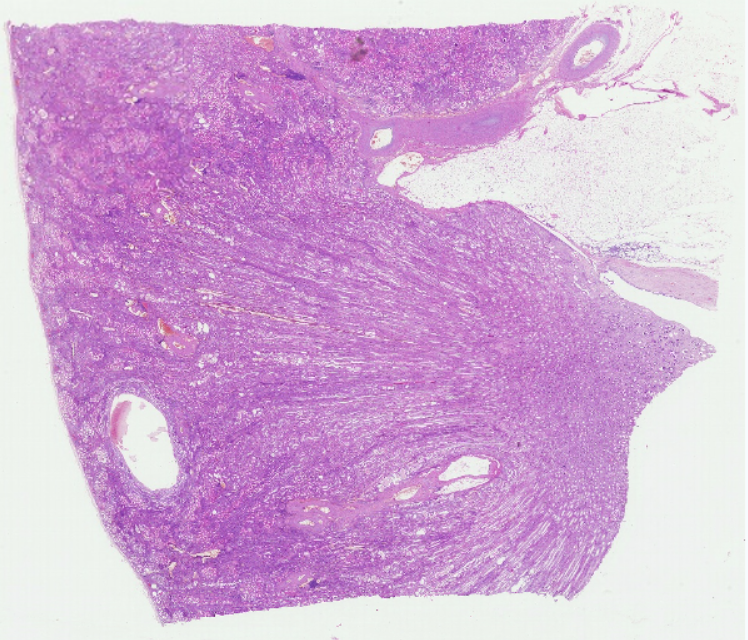

3 慢性硬化性肾小球肾炎

3.肾小球硬化

4.间质血管扩张充血

4.肾小球代偿肥大

5.炎症细胞浸润、纤维增生